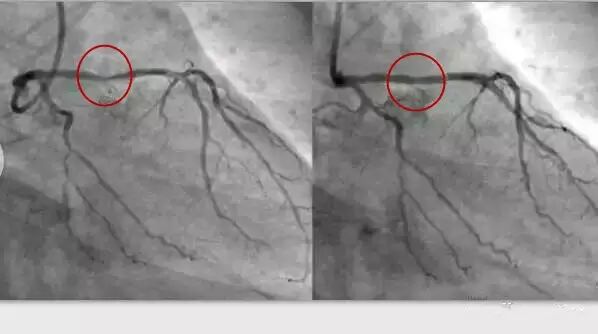

电脑截图,红色区域为狭窄的血管放入支架后变粗,使得血流正常通过。